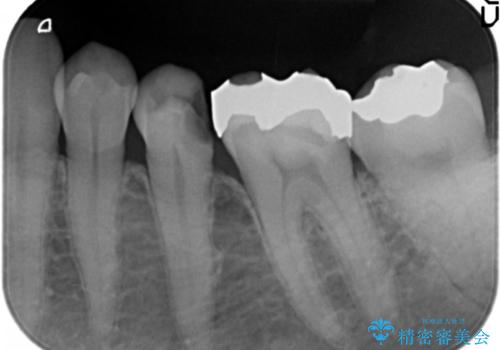

銀歯が外れ、内部に大きな虫歯の再発

- 20年ほど前に治療した虫歯が脱離し、内部には大きな虫歯が認められました。

神経を保存できるよう丁寧に虫歯を除去し、セラミックによる機能回復を計画します。

老朽化した銀歯の下には虫歯の再発リスクが潜んでいます。定期的なX線写真検査が早期発見に有効です。